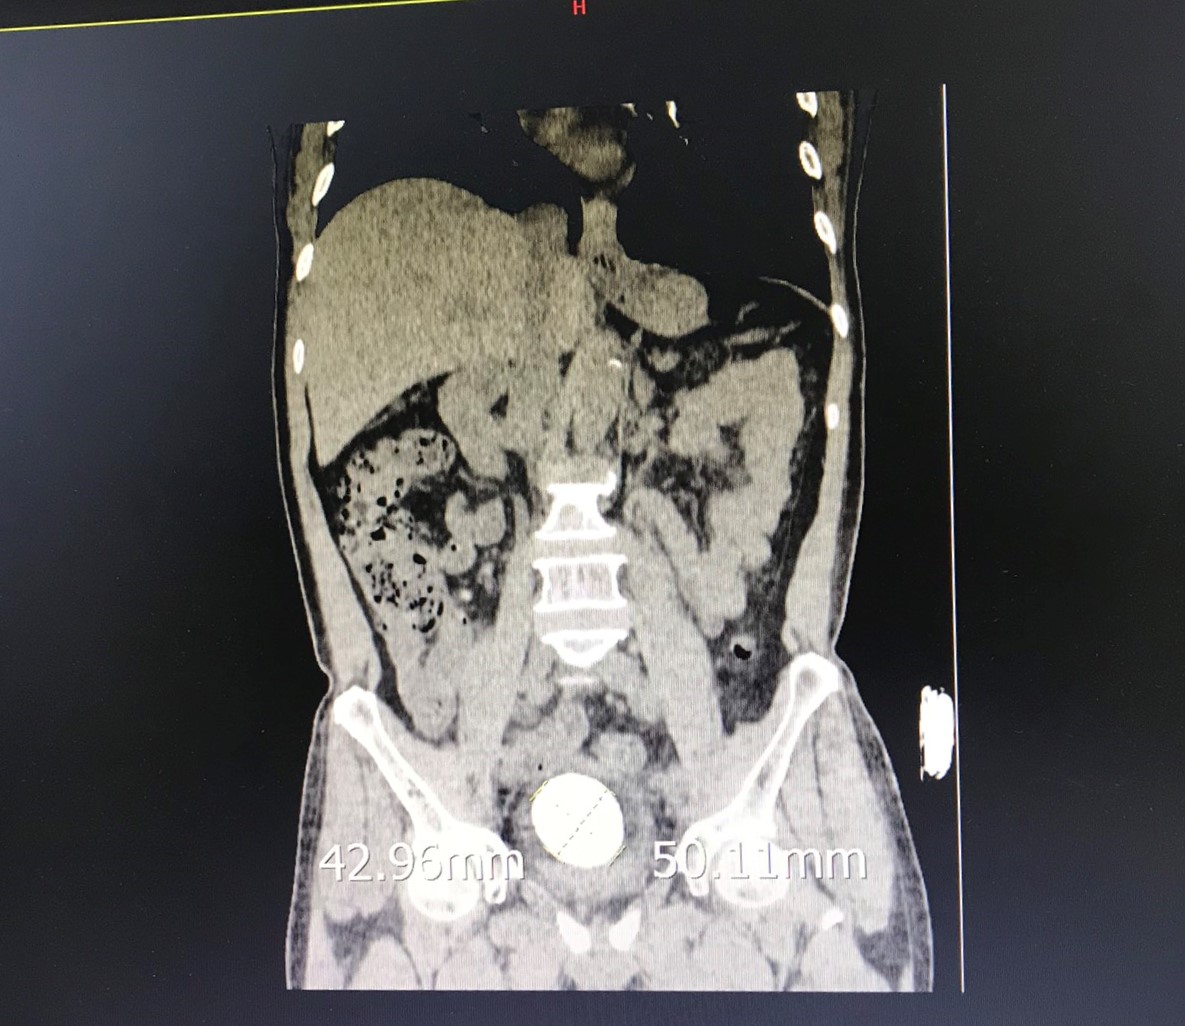

Bệnh nhân T.Q.C, 71 tuổi, ở Hồ Nam, Lê Chân, Hải Phòng xuất hiện đái khó nhiều ngày, đái buốt, rắt, đái tắc, tia tiểu yếu kèm theo có đau tức hạ vị, buốt niệu đạo. Qua thăm khám và thực hiện các cận lâm sàng cần thiết, các bác sĩ Bệnh viện đa khoa Quốc tế Hải Phòng chẩn đoán phát hiện người bệnh có đồng thời nhiều sỏi: sỏi bàng quang kích thước lớn (hơn 5cm), sỏi niệu quản phải 1/3 dưới, kích thước (hơn 1cm), nhiều sỏi trong nhiều túi thừa bàng quang.

Để chấm dứt tình trạng đái buốt, rắt, đau đớn, khó chịu kéo dài và các biến chứng nặng nề có thể xảy ra cho người bệnh, các bác sĩ Khoa Ngoại thận tiết niệu – Nam học đã quyết định tiến hành nội soi tán sỏi cho bệnh nhân. Người bệnh có 01 sỏi nằm choán chỗ toàn bộ bàng quang (kích thước thực tế khoảng 5 x 7 cm) và nhiều sỏi nằm trong túi thừa (03 viên sỏi nằm ở hai túi thừa, vị trí thành sau bên phải, cạnh lỗ niệu quản phải). Đặc điểm sỏi rắn chắc, gai góc và xù xì, khó tán; cổ túi thừa nhỏ niệu quản phù nề gây khó khăn trong quá trình thực hiện. Điều đặc biệt hơn, với kích thước sỏi bàng quang lớn, nếu mổ mở người bệnh sẽ phải chịu một vết mổ dài trên thành bụng và bàng quang để lấy sỏi gây đau đớn, tiềm ẩn nhiều nguy cơ như: chảy máu, nhiễm trùng vết mổ, kéo dài thời gian nằm viện, ảnh hưởng đến sức khỏe và kinh tế cho người bệnh.